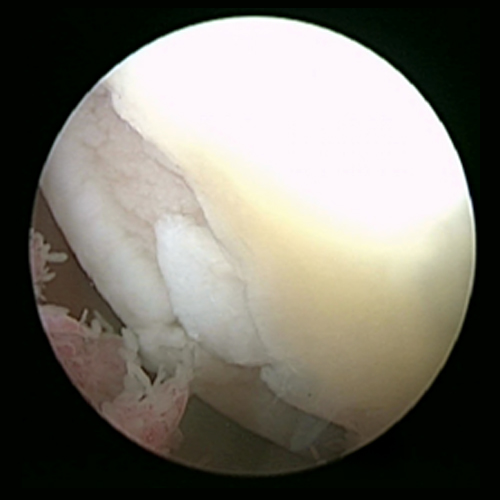

Knorpelschäden des Kniegelenkes

Der hyaline Gelenkknorpel überzieht die Oberfläche der knöchernen Gelenkpartner (Unterschenkel, Oberschenkel und Kniescheibenrückseite) und ist ein einzigartiges Gewebe, welches die Lastübertragung, Lastverteilung sowie ein nahezu reibungsloses Gleiten der Gelenkpartner ermöglicht. Der Knorpel selbst besitzt keine Nervenzellen und kann daher keinen Schmerz vermitteln.

Die Ursachen von Knorpelschäden sind vielfältig, so können Verdrehtraumen (Unfälle), lokale Überbelastungen oder auch Fehlstellungen Knorpelschäden auslösen. Knorpelschäden verursachen meist eine unspezifische Symptomatik. So gehören Ergussbildungen, Funktionseinschränkungen und Schmerzen zu möglichen Symptomen. Die Folge von Knorpelschäden kann ein Verschleiß des Gelenkes (Arthrose) sein.

Zur Knorpelersatztherapie gibt es zurzeit drei verschiedene Therapiekonzepte. Jedes Konzept hat in Abhängigkeit von Patientenalter, Defektgröße, Defektlokalisation und Defektgrad seine Vor- und Nachteile.

Das Grundprinzip der knochenmarkstimulierenden Techniken wie der Mikrofrakturierung (Mfx) ist die lokale Perforation der Grenze zwischen Knorpel und Knochen („subchondrale Grenzlamelle“) im Defektbereich. Aus der Zone unterhalb des Knochens („subchondraler Raum“) kommt es durch die gezielte Perforation zur Einblutung in den Knorpeldefekt. Hier bildet sich eine Art „Blutpropfen“ der Ursprungszellen aus der subchondralen Zone beinhaltet. Nach temporärer Ausbildung eines Granulationsgewebes, entsteht hieraus ein faserartiges Ersatzknorpelgewebe. Die Mikrofrakturierung ist limitiert auf kleine Knorpelschäden und zeigt in jüngeren Studien nach ca. 3-5 Jahren eine deutliche Ergebnisverschlechterung. Aufgrund dessen ist diese Therapieoption aus unserer Sicht nur noch in ausgewählten Fällen zu empfehlen.

Die „Autologe Matrixinduzierte Chondrogenese“ stellt in diesem Zusammenhang eine Weiterentwicklung dar. Nach Perforation wird eine synthetisch hergestellte Matrix, welche meist aus Bestandteilen des Knorpels besteht, in den Defekt eingesetzt. Diese soll als Gerüst und Schutz für den „Blutpropfen“ gegen Scherbelastungen dienen und die Langfristigkeit dieser Therapie verbessern.

Knorpel-Knochentransplantation (Mosaikplastik/OATS-Plastik)

Bei dieser Technik wird zunächst aus wenig belasteten Regionen des Kniegelenkes ein Knorpel-Knochen-Zylinder ausgestanzt. Dieser wird dann in den zuvor ausgestanzten Knorpeldefekt in der Belastungszone wieder eingestanzt. Der Knorpel-Knochen-Zylinder wird also direkt in einer OP von einer Stelle zur anderen Stelle verpflanzt. Verwendet man hierbei mehrere Stanzzylinder, handelt es sich um eine sogenannte „Mosaikplastik“. Wird ein großer Zylinder verwendet, handelt es sich um die „OATS-Plastik“. Da die Fläche der wenig belasteten Zonen des Kniegelenks eingeschränkt sind, ist die Größe der zu behandelnden Knorpeldefekte ebenfalls limitiert. Ihr Einsatzbereich ist bei Knorpel-Knochen-Defekten (z.B. Osteochondrosis Dissecans), da sie die Schädigung des Knochens und des Knorpels gleichzeitig adressiert.

Knorpelzelltransplantation (ACT-„Autologe (körpereigene) Chondrozytentransplantation“)

Die Knorpelzelltransplantation stellt die Therapie der Wahl bei großen Knorpelschäden (>2cm2) da. Es handelt sich um ein zweizeitiges Therapieverfahren. Im Rahmen der ersten Operation in Schlüsselloch-Technik (Arthroskopie) wird Knorpelgewebe aus nicht belasteten Anteilen des Gelenkes entnommen, und dieses anschließend 3-4 Wochen kultiviert.

Im Rahmen einer zweiten OP werden die Knorpelzellen dann in den Knorpelschaden transplantiert. Die Knorpelzellen sind hierbei an ein Trägermaterial (z.B. Gele oder Kollagenvliese) gebunden. Sollte zusätzlich zum Knorpeldefekt auch ein knöcherner Defekt bestehen, kann dieser zunächst mit körpereigenem Knochen aufgefüllt und dann mit einer Knorpelzelltransplantation kombiniert werden. Die Überlegenheit der Knorpelzelltransplantation bei großen Knorpelschäden wurde im Vergleich zu anderen Knorpelersatzverfahren mehrfach wissenschaftlich bestätigt. Junge Patient*innen (18-50 Jahre) mit isolierten Knorpelschäden (keine Gelenkarthrose) kommen für die Behandlung in Frage. Mit ihr verbunden ist ein strikter Nachbehandlungs-/Rehabilitationsplan.

Minced cartilage

Grundsätzlich kann man die Technik des „Minced Cartilage“ (to mince = zerhacken) als eine einzeitige Knorpelzelltransplantation beschreiben. Während der Operation wird gesunder Knorpel aus einem nicht belasteten Anteil des Gelenkes gewonnen und unmittelbar in kleinste Stückchen (Knorpelchips) zerschnitten. Durch das Zerschneiden werden die Knorpelzellen aktiviert und es kommt zum Herauswandern der Knorpelzellen aus den Knorpelchips. Diese Knorpelzellen bauen dann die extrazelluläre Matrix des Knorpels (bestehend aus Kollagen und Proteoglykanen) wieder auf. Direkt im Anschluss werden die Knorpelchips mit einem Gewebekleber in den Knorpeldefekt eingeklebt. Dies kann mit oder ohne Membranabdeckung erfolgen siehe ATOS News).